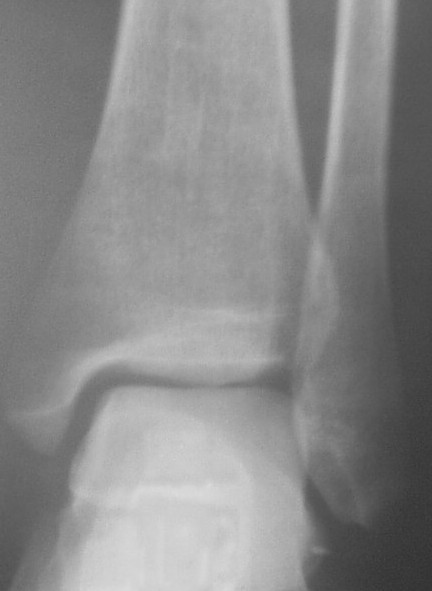

Прямой

На боковом довольно неплохой сустав, скудная информация о положении вилки сустава при косой рентгенограмме (Mortise view) из-за положения стопы во внутренней ротации и эквинуса во время ренгенограммы.

На прямом снимке наружная лодыжка немного укорочена и по описанию на КТ синдесмоз расширен.